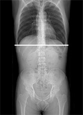

スロットラジオグラフィー(長尺撮影)について

『スロットスキャン』による長尺撮影は、移動しながらほぼ垂直なX線を照射するので歪みが少なく、つなぎ目をなくしたスムーズな全脊椎や全下肢の画像を得ることが可能です。

FPDを搭載しているので従来の全脊椎、全下肢の撮影に比べ、2分の1~10分の1の低線量で撮影することが可能です。

透視台を動かすことで全脊椎、全下肢、全上肢の撮影において、立位・臥位で容易に撮影することが可能です。